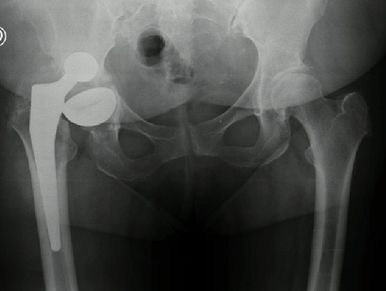

Cirugía de revisión en 2 tiempos, con protesis de cadera personalizada impresa en 3d en Rosario - Dr. Pablo Mariani Rovea